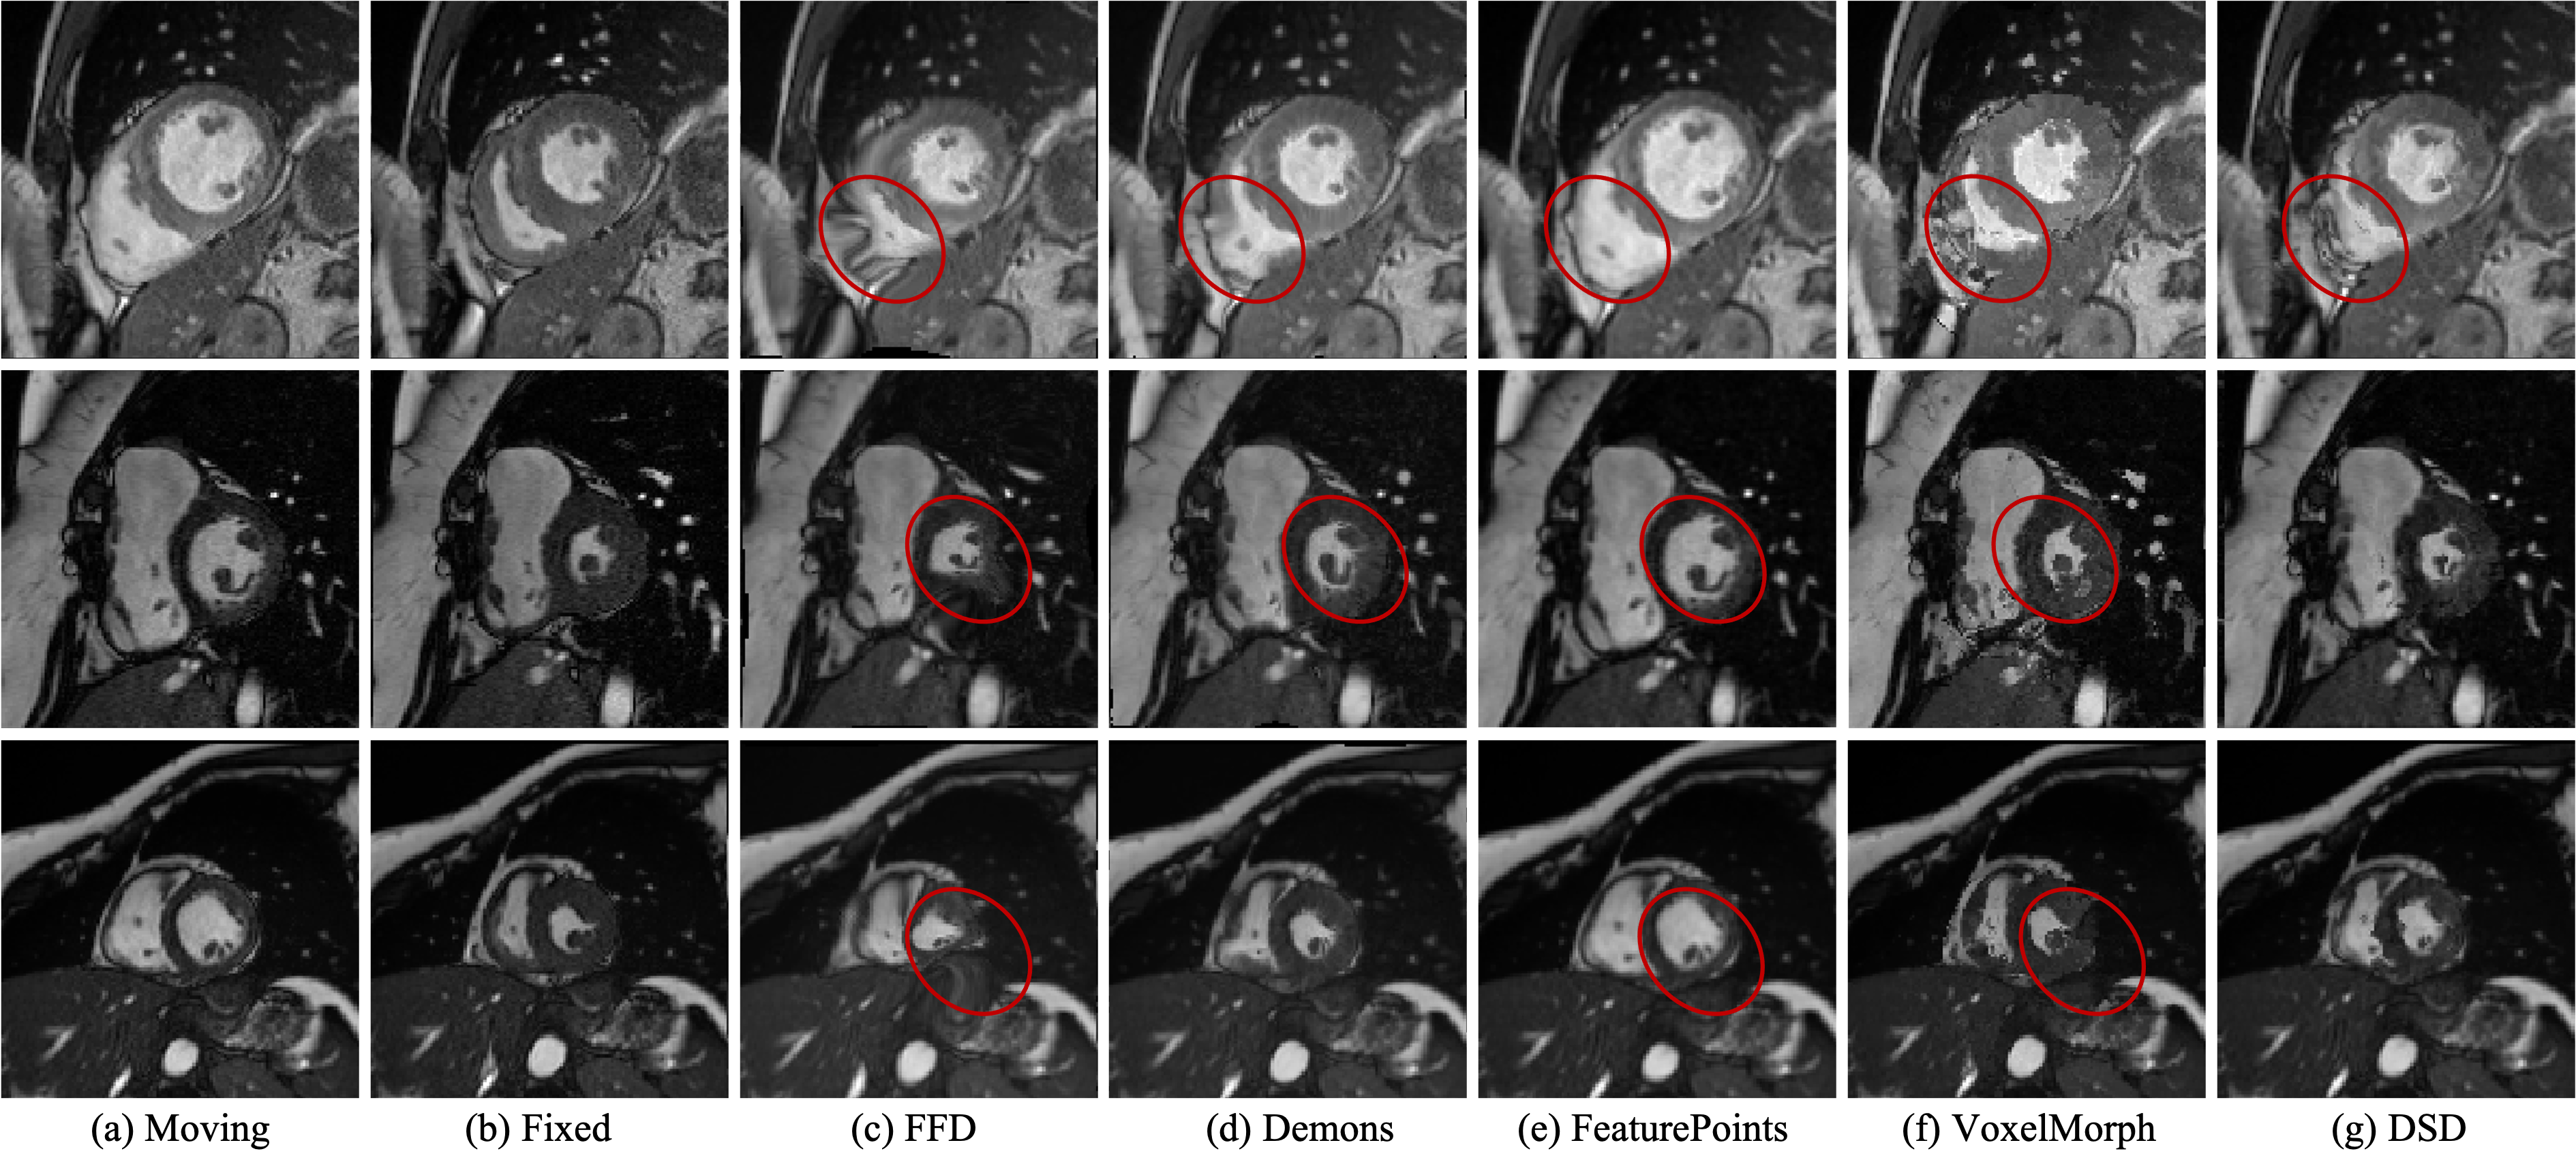

Refer to caption

Figure 10: Visual results of three samples from the ACDC dataset: (a) and (b) indicate the input images; (c) - (f) indicate the deformed moving images by individual methods. The red circles highlight comparisons regarding folding artifacts and errors in the deformed images.

V-A3 ACDC dataset

Table III lists the quantitative motion estimation results on the ACDC dataset. Our proposed DSD method achieves the outstanding performance across most evaluations. As shown in Fig. 10, FFD and Demons are prone to errors in motion estimation. For feature point based method, the moving image is not effectively deformed, because the extracted feature points from the two time-point images lack consistency. Meanwhile, VoxelMorph obtains relatively accurate estimation, but it may still result in folding in image deformation as shown in Fig. 10. In contrast, our proposed DSD method is able to effectively and accurately track the motion in the images.